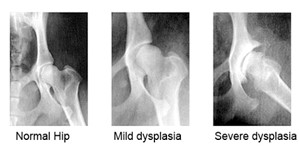

La displasia dell’anca nel Rhodesian Ridgeback

Uno studio sviluppato per OFA dal 1974 al 2010 sull’incidenza della displasia dell’anca in 147 casi ha rivelato che l’incidenza della problematica nel Rhodesian Ridgeback si attesta al 5%, una percentuale relativamente bassa in confronto ad altre razze.

Quando si parla di displasia dell’anca in un cane, ci si riferisce a una malformazione dell’articolazione coxo-femorale, la quale solitamente si presenta e si manifesta durante la crescita del cucciolo. Il cucciolo affetto da questa patologia presenterà una mancata congruenza tra testa del femore e cavità acetabolare comportando un’instabilità nei confronti dei movimenti del cane, con margini articolari che si deteriorano in maniera scorretta; la cartilagine articolare degenera, dando vita all’artrosi cronica accompagnata da dolori.

I sintomi della displasia dell’anca legati a un cane adulto riguardano l’artrosi, ormai sviluppatasi nel corso degli anni. Anche in questo caso, l’intensità del dolore varia secondo la gravità della patologia. Per eseguire una diagnosi corretta bisognerà sottoporre il cane a radiografie mirate, si consiglia una diagnosi precoce intorno ai 4 -6 mesi di vita, una procedura particolarmente utile, poiché esistono interventi di tipo correttivo che possono essere applicati solo in fase di crescita non compiuta. Tale diagnosi è emessa da un veterinario ortopedico a seguito di visita clinica, osservazione dell’andatura e della postura, manipolazione e radiografie con sedazione. A seguito del risultato emerso dalla radiografia, è possibile definire il grado di displasia dell’anca, ovvero:

Grado A, non c’è displasia dell’anca partendo dalla testa del femore fino ad acetabolo e congruenti;

Grado B, l’articolazione dell’anca si presenta quasi normale, mentre la testa del femore e l’acetabolo sono di poco incongruenti;

Grado C, ove sarà diagnostica una leggera displasia dell’anca, con testa del femore e acetabolo incongruenti e piccoli segni artrosici;

Grado D, ovvero media displasia dell’anca, con testa del femore e acetabolo evidentemente incongruenti e presenza di artrosi;

Grado E, grave displasia dell’anca, con importanti modificazioni dell’anca e possibile lussazione o sub lussazione della medesima. Inoltre, si avrà un’importante deformazione della testa del femore, che si presenterà a fungo o appiattita, oltre alla presenza di una forte artrosi.